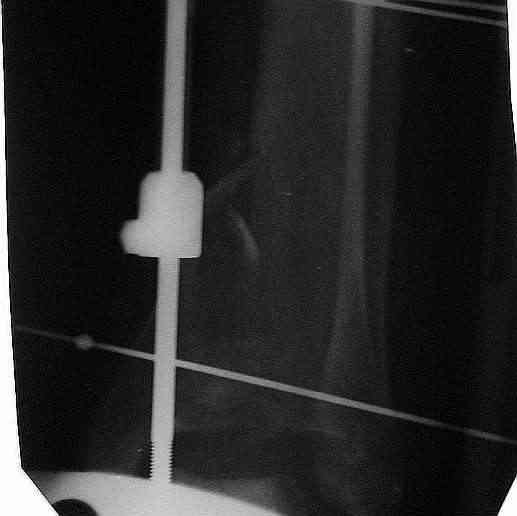

Здравствуйте, коллеги.Больной 26 лет, в 2004 году попал ко мне с диагнозом:синтезированный в аппарате Илизарова неполный внутрисуставной оскольчатый перелом дистального метафиза левой большеберцовой кости со смещением; выраженный остеопороз; множественное спицевое нагноение. Несостоятельность фиксации (костные отломки буквально "елозили" по спицам, несмотря наналичие упорных площадок).

Мной был демонтирован АВФ, удалены все спицы. Больной некоторое время лечился консервативно (шина Белера, антибиотики, перевязки). По заживлению и купировании гнойно-воспалительного процесса была произведена осткрытая репозиция, накостный остеосинтез 1/3 трубчатой пластиной.Такой вариант был принят из-за жуткого остеопороза и отказом больного от предложенного артродезирования голеностопного сустава сразу. Послеоперационный период без особенностей. Через год, больной пришел на осмотр на своих двоих, без дополнительной опоры, с жалобами на боли приходьбе в обл. г/стопа и с желанием замкнуть сустав. В операционной столкнулся с неожиданной проблемой по удалению пластины, она была глубоко вмурована в толщу склерозированного метафиза на глубину 1.5 см; удалить не рискнул (считал, что металл помешает в ходе реконструкции и требуется его удаление).

Было решено, уже по ходу операции, выполнить артродез болтом-стяжкой, тем самым компрессируя резецированные суставные поверхности и смещая стопу латерально, дабы нивелировать варусную деформацию и восстанавливая тем самым опорную ось всей конечности.

Вчера (прошло около 8 месяцев)больной обратился ко мне в очередной раз с жалобами на боли умеренно-жгучего характера в области выстояния концов болта-стяжки. На момент осмотра:укорочение левой нижней конечности на 1,5 см; гипотрофия медиальной группы мышц голени и четырехглавой мышцы бедра; передвигается без дополнительной опоры в ортопедической обуви на растояние до 5 км; работает приемщиком цветных металлов (приходится перетаскивать грузы). Нарентгенограмме, насколько это можно видеть, костного блока сформировать не удалось, но движений в голеностопном суставе нет - ни активных, ни пассивных. Послеоперационные рубцы б/о; свищей и нагноения не было. Активно больногонаблюдать не приходилось, т.к. проживает в другом городе.

ЗЫ: Прошу прощения за очень низкое качество представленных ренгенограмм. Буду очень признателен за комментарии.